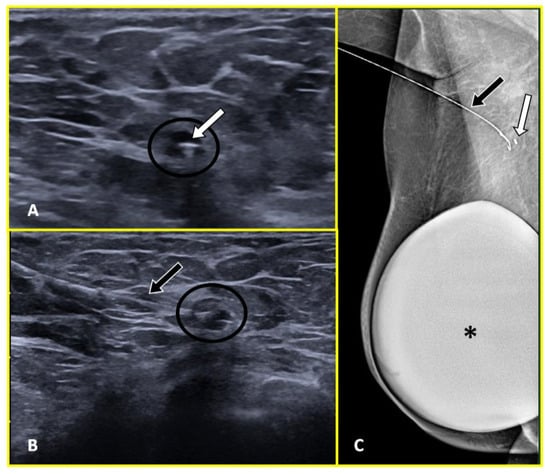

2.3. Metal Wires